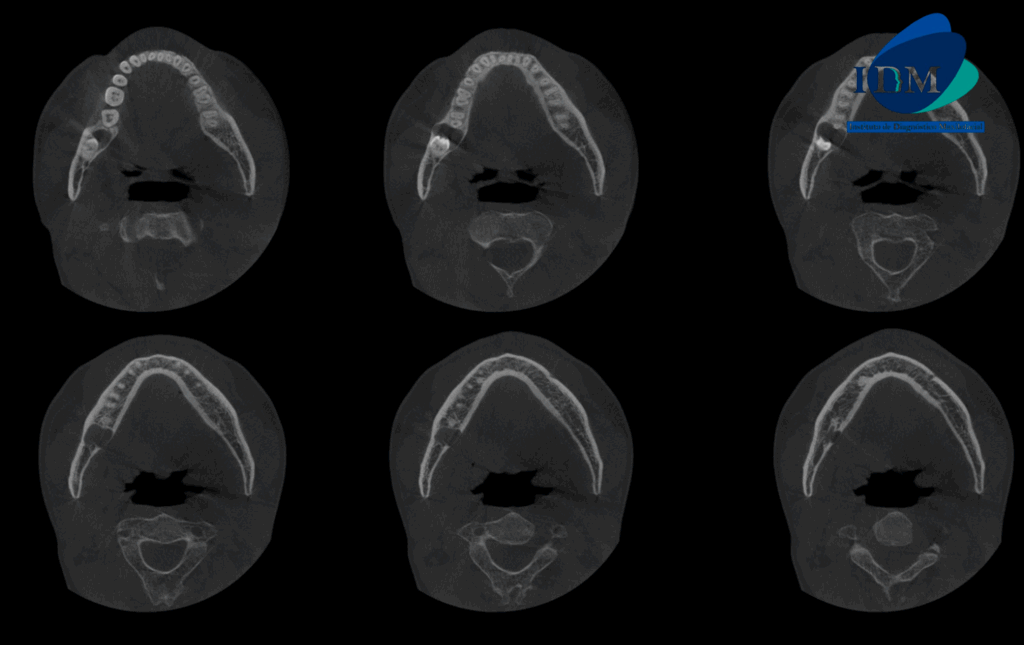

A la evaluación de la tomografía volumétrica (CBCT) en los cortes axiales (Figura 2) y transaxiales (Figura 3), se aprecia imagen hipodensa peri coronaria, de limites definidos, bordes corticalizados, que se extiende en sentido cefálico caudal desde cima del reborde alveolar hasta cortical inferior del conducto dentario inferior, en sentido mesio distal desde distal de pieza 47 hasta tercio medio coronal de pieza 48, ocasionando el borramiento parcial de lamina dura de pieza 47 y cortical superior del conducto dentario inferior, adelgazamiento de tabla ósea vestibular y lingual.

CORTES AXIALES